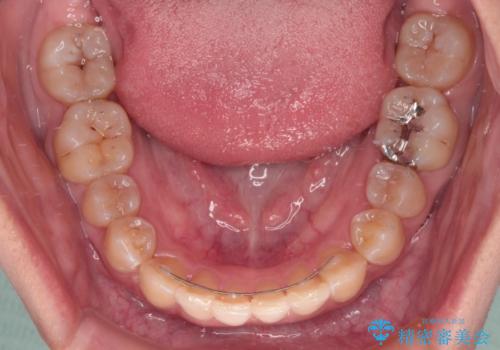

【モニター】下顎前歯のデコボコをインビザラインできれいに

下顎前歯のデコボコが集中しており、奥歯の咬み合わせは、上顎に対して下顎が前方位にある状態でした。下顎の歯列を後方へ移動させる治療はインビザラインの得意とするところですので、1年程度で無事に治療を終えることができました。